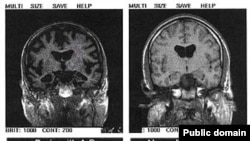

سمت چپ: مغز فرد دچار به آلزایمر، سمت راست: مغز فرد غیرمبتلا به آلزایمر

اداره کنترل کیفیت دارو در آمریکا روز دوشنبه ۱۷ خرداد با وجود بحث‌برانگیز بودن نتایج آزمایش‌های بالینی، داروی جدید شرکت داروسازی «بایوژن» برای درمان یکی از عوامل اساسی بروز بیماری آلزایمر را تأیید کرد.

به گزارش خبرگزاری رویترز، سازندگان این دارو به نام «ادوکانومب» می‌گویند قادر است رسوبات پروتئین چسبنده‌ای به نام «آمیلوید بتا» را در مراحل اولیه بروز آلزایمر از مغز بیماران جدا و پاک کند و در نتیجه از بروز عوارض شدید این بیماری جلوگیری کند.

اداره کنترل کیفیت دارو در آمریکا گفت نتایج آزمایش‌های بالینی نشان می‌دهد که این دارو باعث کاهش پلاکت‌ها می‌شود و انتظار می‌رود که این تغییر زوال سلامتی مبتلایان به آلزایمر را کاهش دهد. این دارو قرار است با نام تجاری «ادوهلم» (Aduhelm) به بازار عرضه شود.

این نهاد در بیانیه خود خاطرنشان کرد: «هر چند داده‌های موجود در مورد فواید ادوهلم پیچیده است ولی به این نتیجه رسیده‌ایم که این دارو در کاستن از پلاکت‌های آمیلوید بتا در ناحیه مغز مؤثر است و به احتمال فراوان کاهش این پلاکت‌ها برای بیماران فواید مهمی خواهد داشت.»